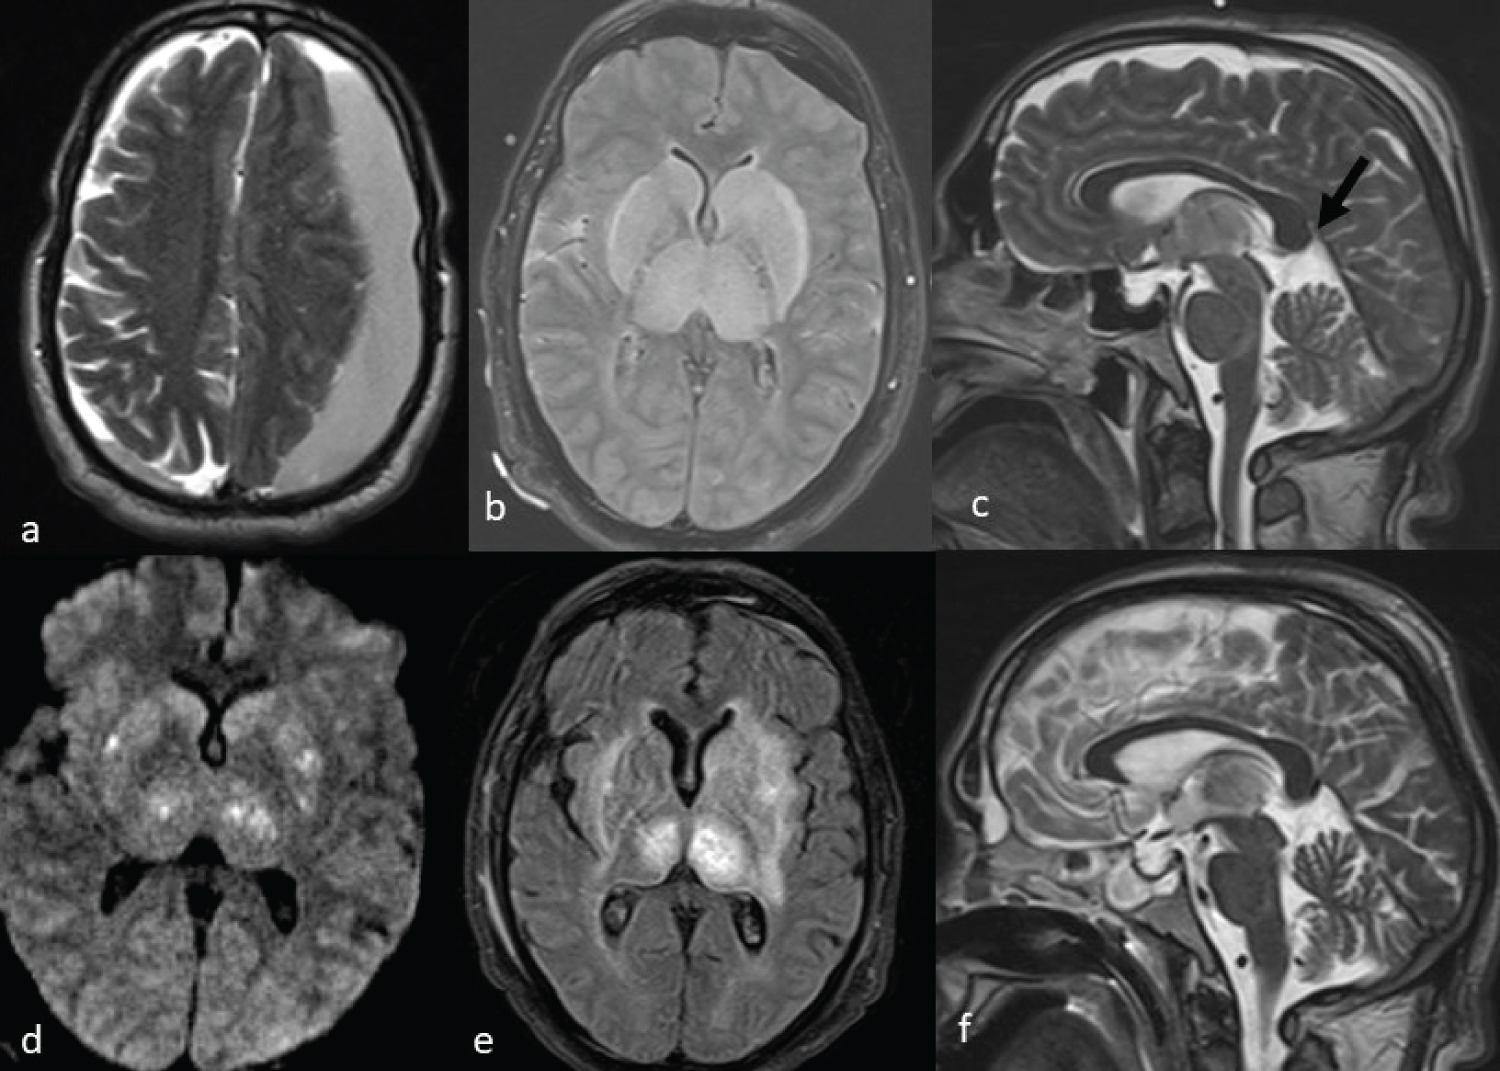

An 86-year-male presented with weakness in right upper and lower limb for two days, which had increased on the day of admission. He had a past history of coronary artery disease, psoriasis and hypothyroidism. He had been operated for normal pressure hydrocephalus a year ago and had a programmable shunt in situ . On examination, the patient was conscious but confused. Pupils were bilaterally equal and reacting to light. He had slurring of speech with right hemiparesis (power 4/5 in upper and lower limb). MRI brain (Figure 1a and Figure 1b) revealed a large SDH along the left cerebral convexity causing mass effect and midline shift and a thin SDH along the right cerebral convexity. The vital parameters, blood investigations, ECG and chest X-ray were normal. The patient underwent a left frontotemporoparietal craniotomy and evacuation of SDH under general anaesthesia and a subgaleal drain was left in situ . Intraoperative period was uneventful. Postoperatively, the patient was breathing spontaneously but there was no return of consciousness or reflexes. Non-contrast computed tomography (NCCT) head was done in the operation theatre which showed no fresh bleed. Thereafter, he was shifted to intensive care unit on ventilator. The patient did not show any improvement in sensorium even after four hours and GCS remained E1VTM1. MRI brain (Figure 1c, Figure 1d, Figure 1e, Figure 1f, Figure 1g and Figure 1h) was done which revealed extensive oedema with diffusion restriction involving bilateral cerebellum, pons, midbrain and left frontoparietal region. A posterior fossa decompression was planned but the family did not give consent. He was therefore managed conservatively with hyperosmolar therapy, Trendelenburg position and ventilatory support. The clinical condition did not improve and he developed refractory hypotension and died the following day.

Figure 1: T2W and T1W MRI image (a&b) showing large chronic left frontoparietal subdural hematoma. Post-operative DWI MRI (c,d,g&h) showing large areas of diffusion restriction involving bilateral parieto-occipital regions, cerebellum, thalamus and brain stem, suggesting irreversible damage. Post-operative sagittal T2W MRI image (e) showing distorted and pointed splenium (black arrow) compressing the vein of Galen. Flair MRI image (f) showing signal change and swelling in bilateral thalamus.

DWI: Diffusion Weighted Image; MRI: Magnetic Resonance Imaging; T1W: T1 Weighted; T2W: T2 Weighted. View Figure 1